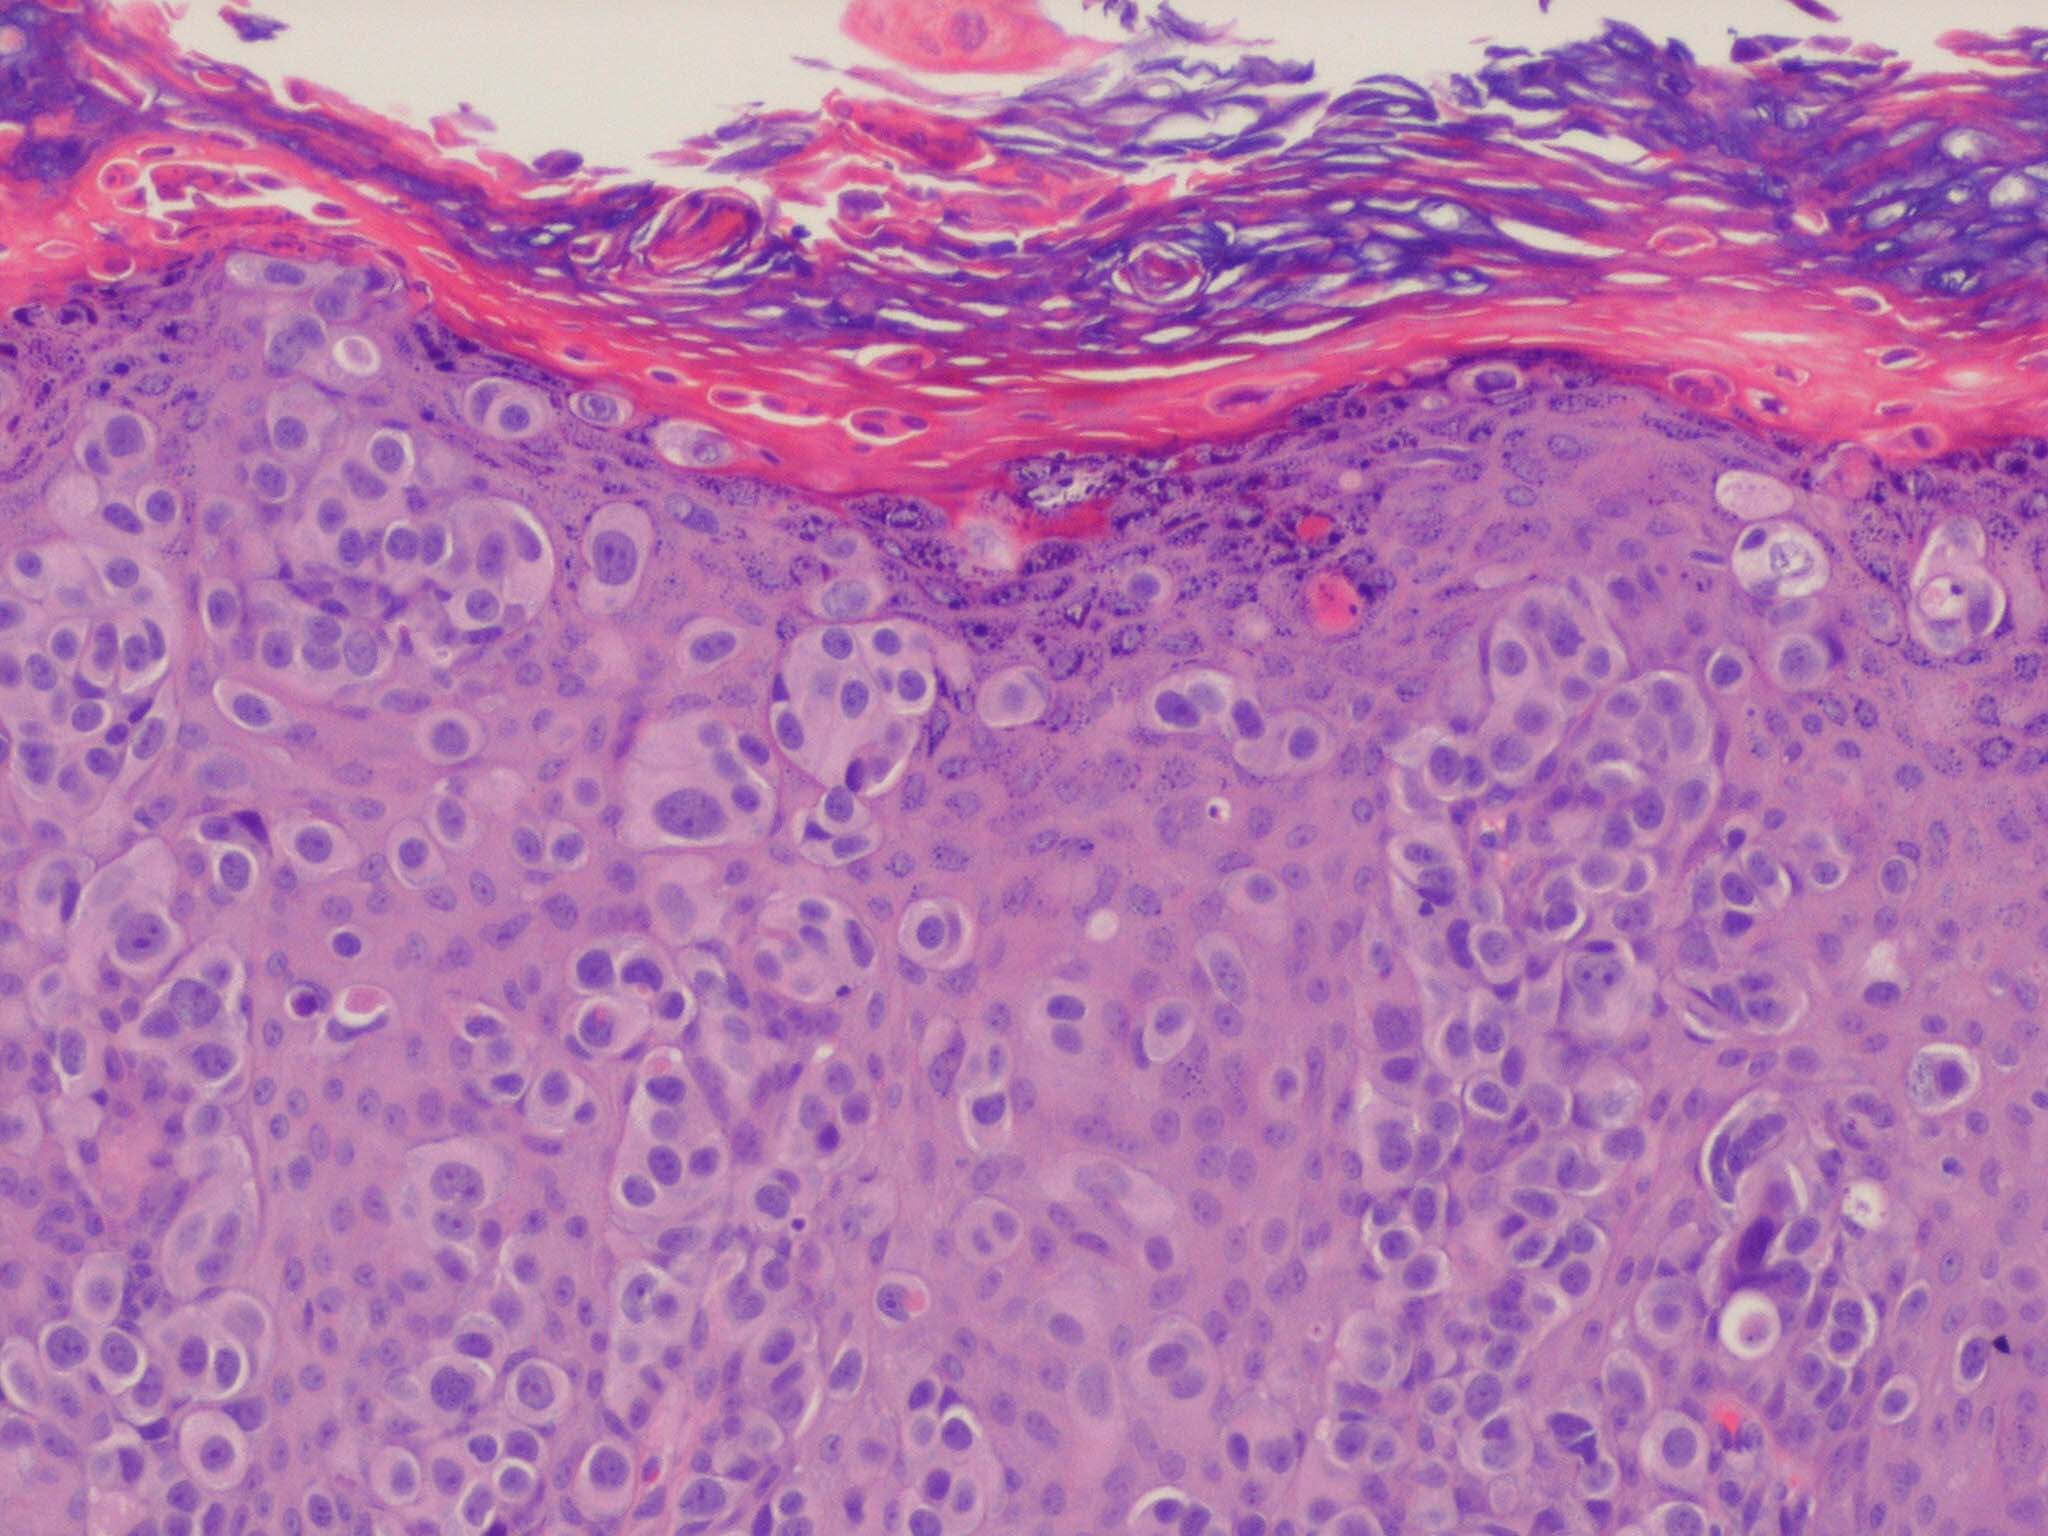

Paget disease = داء باجت